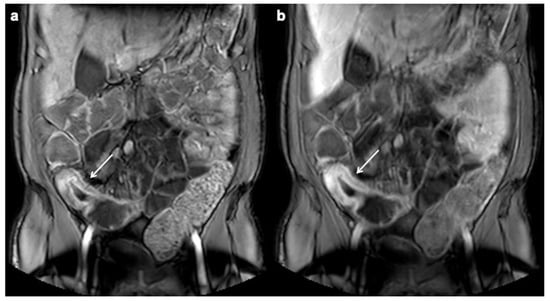

- Rimola, J.; Planell, N.; Rodríguez, S.; Delgado, S.; Ordás, I.; Ramírez-Morros, A.; Ayuso, C.; Aceituno, M.; Ricart, E.; Jauregui-Amezaga, A.; et al. Characterization of Inflammation and Fibrosis in Crohn’s Disease Lesions by Magnetic Resonance Imaging. Am. J. Gastroenterol. 2015, 110, 432–440. [Google Scholar] [CrossRef]

- Foti, P.; Travali, M.; Farina, R.; Palmucci, S.; Coronella, M.; Spatola, C.; Puzzo, L.; Garro, R.; Inserra, G.; Riguccio, G.; et al. Can Conventional and Diffusion-Weighted MR Enterography Biomarkers Differentiate Inflammatory from Fibrotic Strictures in Crohn’s Disease? Medicina 2021, 57, 265. [Google Scholar] [CrossRef] [PubMed]

- Tielbeek, J.A.W.; Ziech, M.L.W.; Li, Z.; Lavini, C.; Bipat, S.; Bemelman, W.A.; Roelofs, J.J.T.H.; Ponsioen, C.Y.; Vos, F.M.; Stoker, J. Evaluation of conventional, dynamic contrast enhanced and diffusion weighted MRI for quantitative Crohn’s disease assessment with histopathology of surgical specimens. Eur. Radiol. 2013, 24, 619–629. [Google Scholar] [CrossRef]

- Barkmeier, D.T.; Dillman, J.R.; Al-Hawary, M.; Heider, A.; Davenport, M.S.; Smith, E.A.; Adler, J. MR enterography–histology comparison in resected pediatric small bowel Crohn disease strictures: Can imaging predict fibrosis? Pediatr. Radiol. 2015, 46, 498–507. [Google Scholar] [CrossRef] [PubMed]

- Caruso, A.; Angriman, I.; Scarpa, M.; D’Incà, R.; Mescoli, C.; Rudatis, M.; Sturniolo, G.C.; Schifano, G.; Lacognata, C. Diffusion-weighted magnetic resonance for assessing fibrosis in Crohn’s disease. Abdom. Radiol. 2019, 45, 2327–2335. [Google Scholar] [CrossRef] [PubMed]

| Stricture |

| Fibrofatty proliferation |